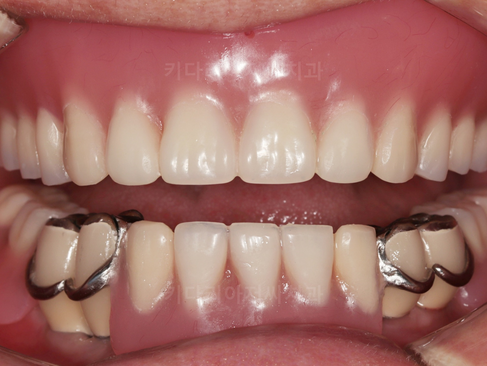

위쪽 완전틀니와 아래쪽 부분틀니+보험임플란트가 모두 완료된 사진입니다.

위쪽 완전틀니와 아래쪽부분틀니, 보험임플란트가 모두 완료된 측면사진입니다.

전보다는 안모도 개선되고, 웃는 모습도 자연스러워진 모습을 확인할 수 있습니다. 환자분도 모든 진료가 마무리되고 만족도가 더욱 높았던 치료입니다.